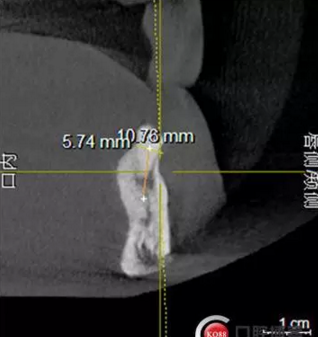

檢查:上頜無(wú)牙頜假牙穩(wěn)定性尚可,下頜3435364243殘根;33殘冠1-2度松動(dòng),其他牙齒缺失;CBCT檢查:下頜牙槽骨前牙區(qū)骨高度足,后牙區(qū)骨高度最低為8mm,骨寬度足。

1)術(shù)前檢查,拍攝臨床照片及CBCT檢查,制取活動(dòng)義齒參考模型,指導(dǎo)后期最終修復(fù)的牙齒排列

2)術(shù)前準(zhǔn)備及手術(shù)過(guò)程,測(cè)量血壓及血糖,簽種植知情同意書;嚴(yán)格遵循無(wú)菌操作,局麻下采用微創(chuàng)技術(shù)于323436分別植入osstem4.0X10,4.0X10,4.5X7; 434446分別植入osstem4.0X1O,4.0X10,4.5X7.初期穩(wěn)定性均達(dá)到了35N.CM以上;嚴(yán)密縫合,止血,種植體位點(diǎn)和方向與設(shè)計(jì)一致。